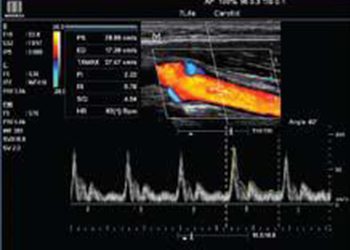

color-doppler

Color Power Doppler

The Color Power Doppler examination visualizes the complex flow of blood through vessels and organs of the human body in real-time.